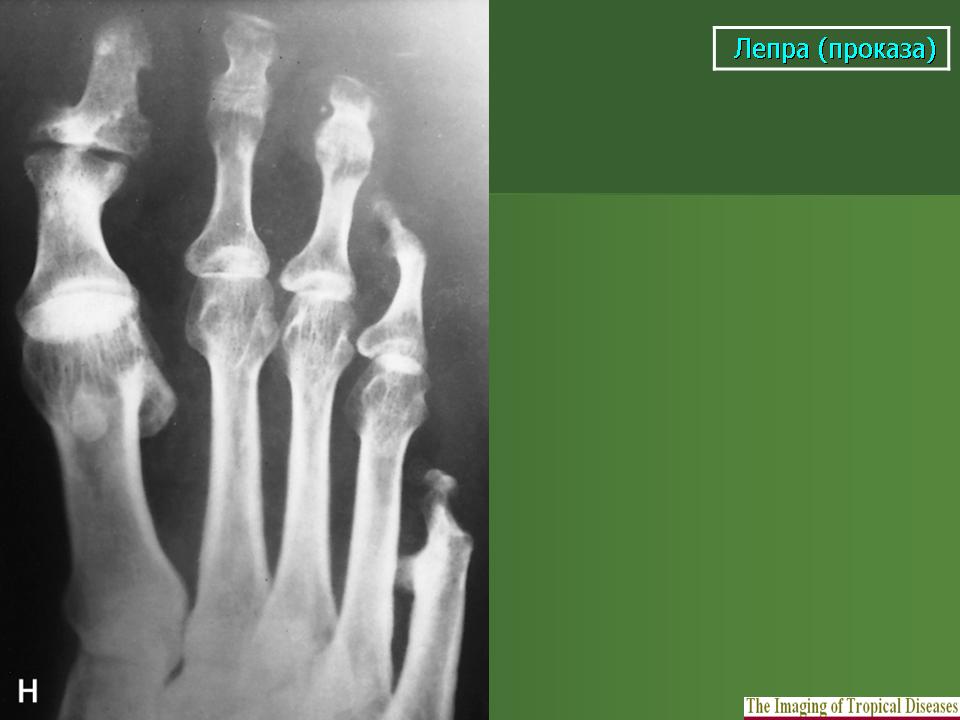

Рентгенологически специфические лепрозные оститы наблюдаются в виде (рис. 215) рассеянных множественных изолированных друг от друга очагов разрушения в корковом и преимущественно губчатом веществе эпифизарных и метафизарных концов фаланг, пястных и плюсневых костей. Реже они гнездятся в диафизах. Это резко очерченные округлые или чаще овальные просветления на месте рассасывания костной ткани бациллонесущей гранулойатозной тканью. Величина очагов в губчатом веществе колеблется от 2 до 8 мм в наибольшем длиннике, в корковом же веществе просветления меньше - до 3 мм в диаметре. Характерны весьма четкие контуры, окаймляющие костные изъяны.

Лепромы вызывают истончение коркового слоя, в результате чего могут возникнуть - надломы и переломы, не имеющие склонности к заживлению обычной костной мозолью. Очень характерны в окружности поверхностно расположенных гранулой периоститы малых трубчатых костей, вызывающие подчас даже некоторое вздутие кости. Г. Е. Живо-товский считает весьма показательным для этой формы проказы, т. е. для сочетания кожных и костных поражений, еще довольно резко выраженные муфтообразные оссифицирующие периоститы и остеопериоститы костей голени и в особенности- симметричные пластинчатые периоститы периферических отделов малоберцовых костей. 1Как известно, симметричные изолированные надкостничные наслоения именно этой локализации, т. е. на малоберцовых костях, не встречаются при других заболеваниях и поэтому приобретают известное диференциально- диагностическое значение.

Очаговое разрушение эпифизарных концов костей развивающимися лепромами влечет за собой также характерное изменение суставов, а именно подвывихи и вывихи, т. е. более или менее тяжелые деформации. Лепроматозные дефекты костей, по наблюдениям Г. Е. Животов-ского, отличаются стойкостью и при лечении не замещаются костной тканью.